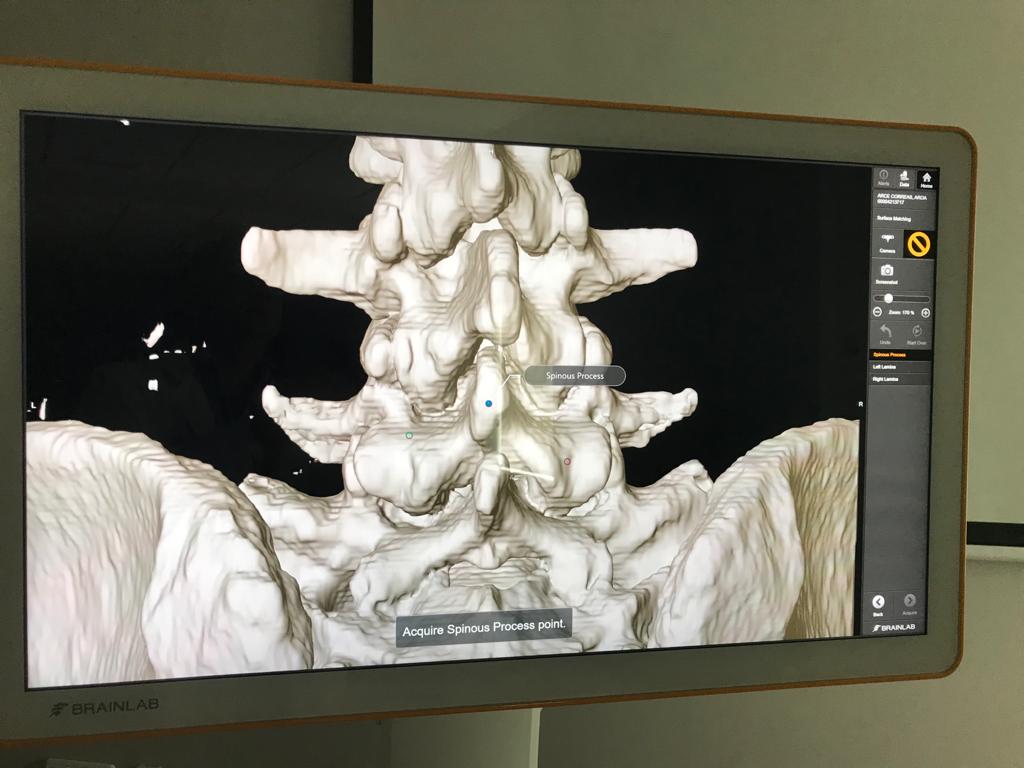

El nuevo sistema digital, integra directamente el software en el quirófano, lo que crea un flujo continuado con la información del paciente, que se actualiza en tiempo real, y ayuda a los especialistas a controlar mejor las intervenciones. Está equipado con una pantalla táctil capacitativa de 32”, que permite visualizar imágenes con una resolución 4K, con un alto nivel de detalle. Esto permite planificar, revisar, documentar y transmitir la intervención, vía streaming, desde cualquier parte del quirófano del Hospital.

“Resulta especialmente preciso en cirugías de columna, ya que mejora la fiabilidad de implantación de tornillos y de cajas. Además, coloca con mayor seguridad los implantes, especialmente en las áreas anatómicas más críticas, con una gran fiabilidad”, asegura el doctor Sánchez.

“Utiliza un nuevo sistema de navegación quirúrgica, más potente que los que se utilizan actualmente. Envía, en tiempo real, imágenes de mayor calidad desde el ecógrafo. Esto nos ofrece una mayor precisión que la cirugía guiada por imágenes, y nos permite planificar la cirugía, antes y durante la intervención, o realizar la navegación de implantes o instrumentos en cualquier momento, desde la planificación de la incisión hasta la colocación de los implantes”, señala el especialista.

El Hospital continuará utilizando este nuevo sistema de navegación inteligente, llamado Curve, y desarrollado por la empresa Brainlab, en próximas intervenciones de columna. Como complemento a esta plataforma, tiene previsto la instalación de un escáner digital, que permitirá realizar la navegación a través de un TAC intraoperatorio, lo que supondrá un gran avance hacia la consolidación de la cirugía digital.